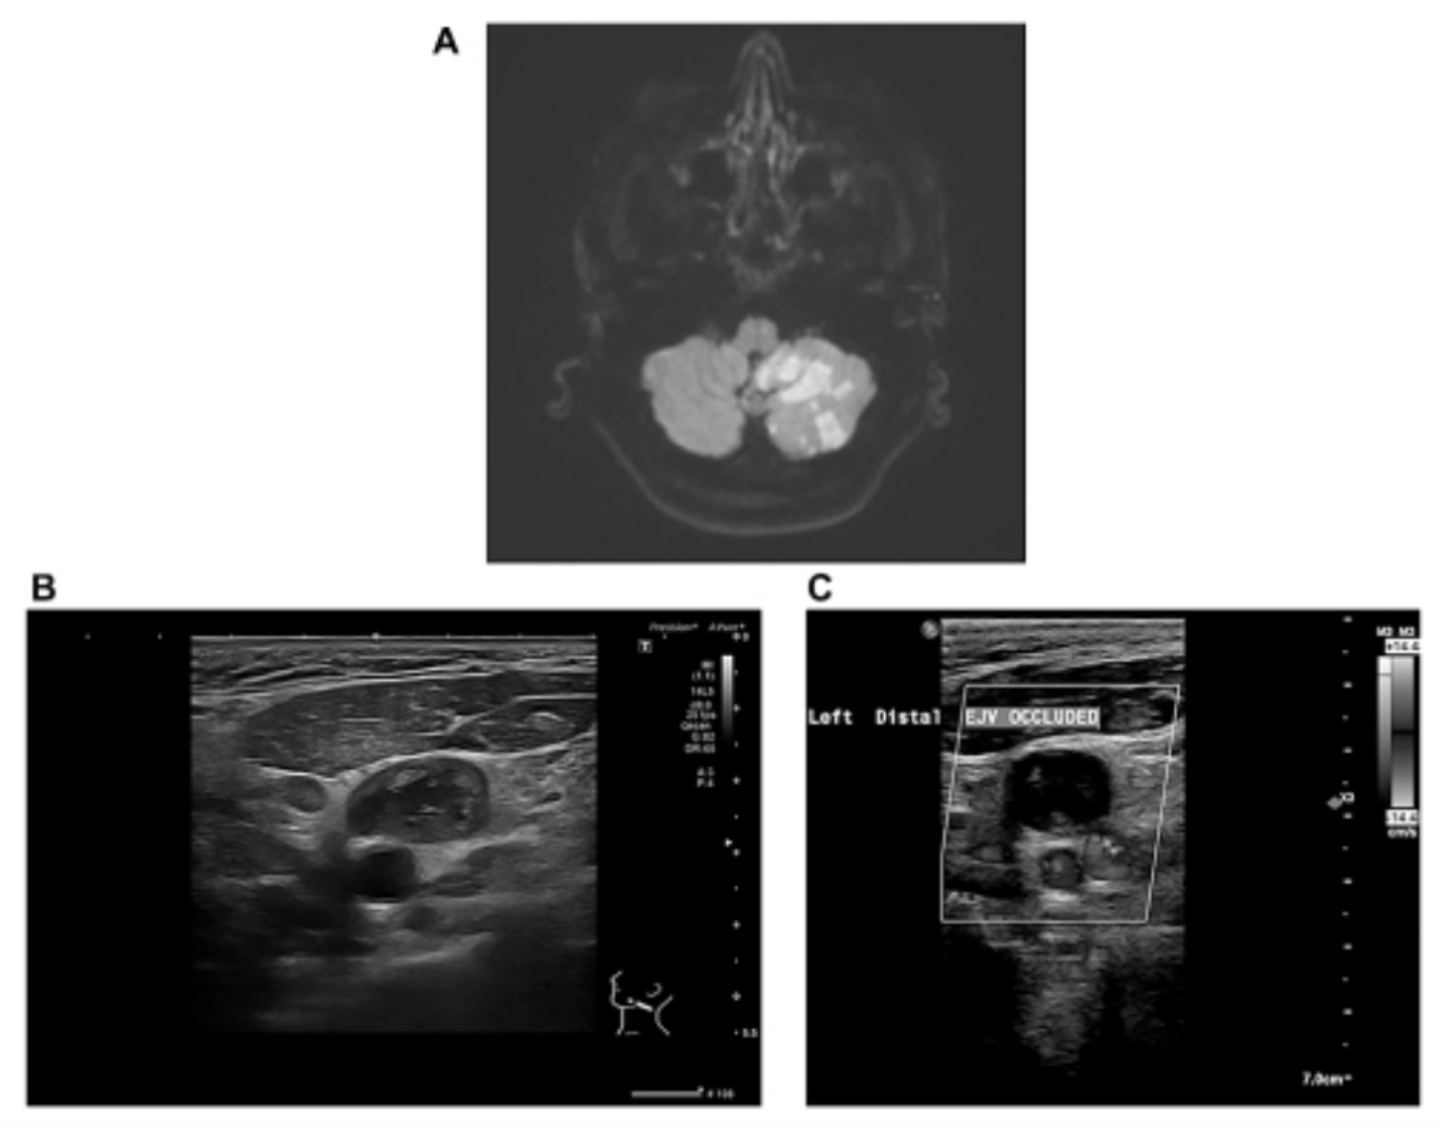

5-FU Chemotherapy Linked to Rare Brain Toxicity in Cancer Patient

“The patient’s symptoms resolved after permanently stopping 5-FU and administering lactulose and intravenous fluids, therefore supporting the diagnosis of hyperammonemic encephalopathy due to 5-FU.” BUFFALO, NY — February 5, 2026 — A new case report was published in Volume 12…